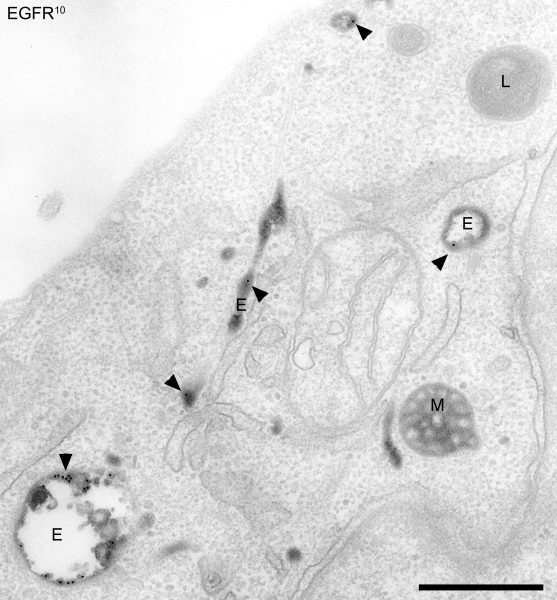

Lo studio, condotto tra Sicilia e Stati Uniti, è stato pubblicato oggi sulla rivista scientifica Nature Communications e potrebbe dare una speranza anche per la cura dei tumori. “Il nucleo è il centro di comando della cellula, contiene Dna protetto da una speciale membrana – spiega il professore palermitano Aurelio Lorico dell’Università di Touro, in Nevada -. La maggior parte dei virus ha bisogno di accedere al nucleo per creare nuove copie di se stesso e invadere altre cellule. Il nostro studio – sottolinea – ha svelato che l’Hiv può entrare nella cellula avvolto all’interno di un pacchetto di membrane che proviene dalla cellula infetta. Questi pacchetti sono chiamati ‘endosomi’. Il virus, avvolto nell’endosoma, viaggia verso l’esterno della membrana nucleare e la spinge verso l’interno per formare ciò che chiamiamo ‘invaginazioni nucleari'”.

“L’endosoma contenente il virus – spiega Lorico – si sposta dentro l’invaginazione nucleare e da qui nel nucleo. Abbiamo scoperto un complesso di tre proteine, Vap-A, Orp3 e Rab7, necessarie perché ciò avvenga”.